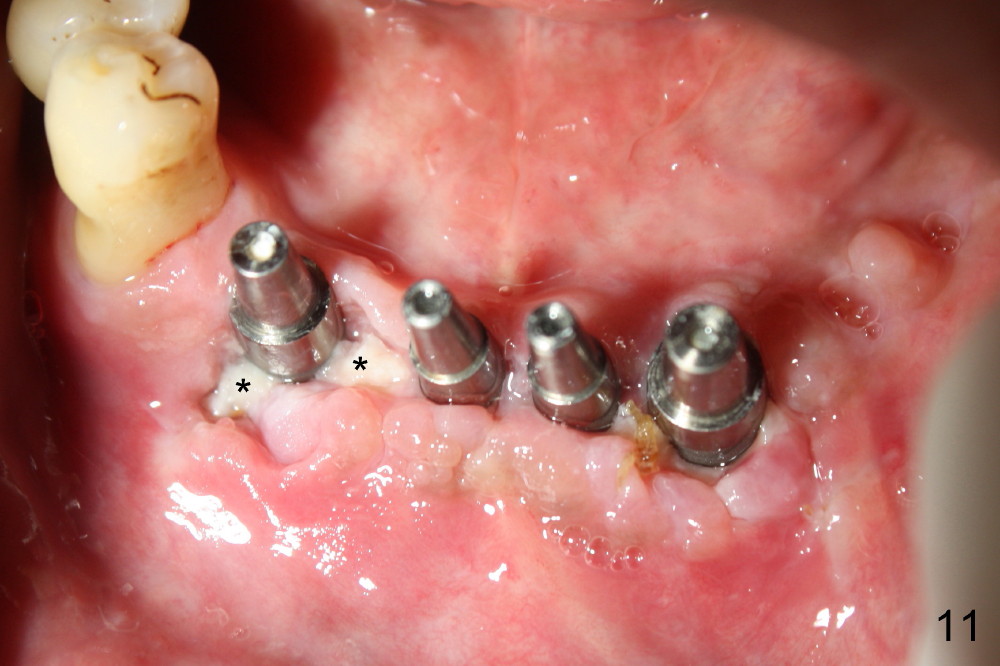

Once the patient improves oral hygiene as instructed, the wound around the implants begins to heal (Fig.10,11) one week later, while that continues healing around guided tissue regeneration area (Fig.12).